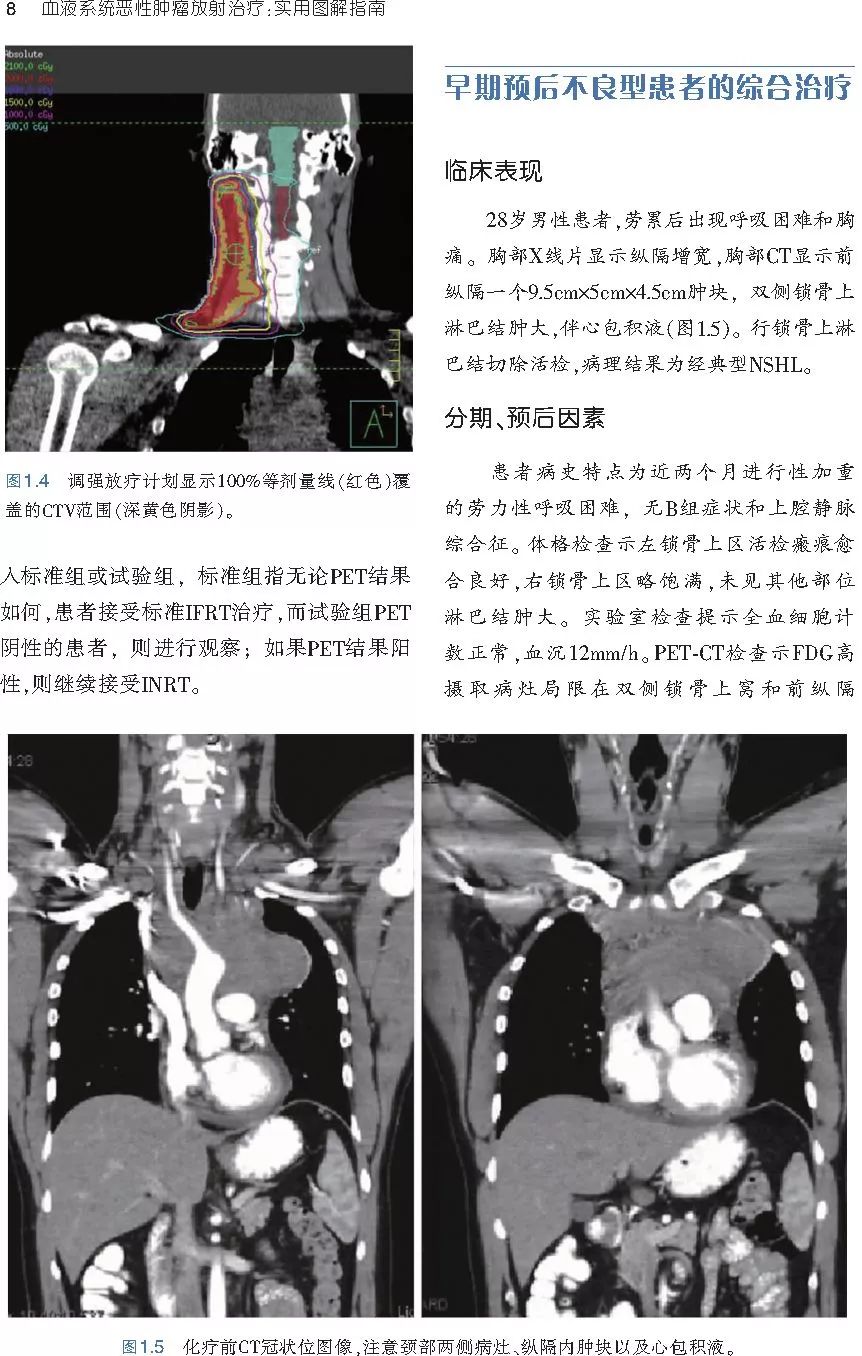

❤ 展开疾病诊断、病理描述及治疗方向的详细阐述,包含医学影像,图文并茂,深入浅出。

本书案例讨论遵循标准格式,包括临床描述,其次是与诊断相关的病理描述和分期,然后详细讨论治疗选择。最后,确定治疗方案,并提供所使用的规划放疗技术/方式的图像。对放射肿瘤医生进行临床决策非常有帮助,对于血液病临床医生也有很好的指导作用。